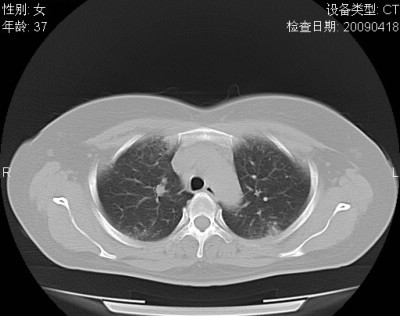

以下是引用随光逐影在2009-4-20 8:03:00的发言:[br]两肺间质性病变(间质性肺炎?特发性肺间质纤维化?)。

以下是引用51736011在2009-4-21 16:24:00的发言:[br]两肺间质性病变(间质性肺炎?特发性肺间质纤维化?)。